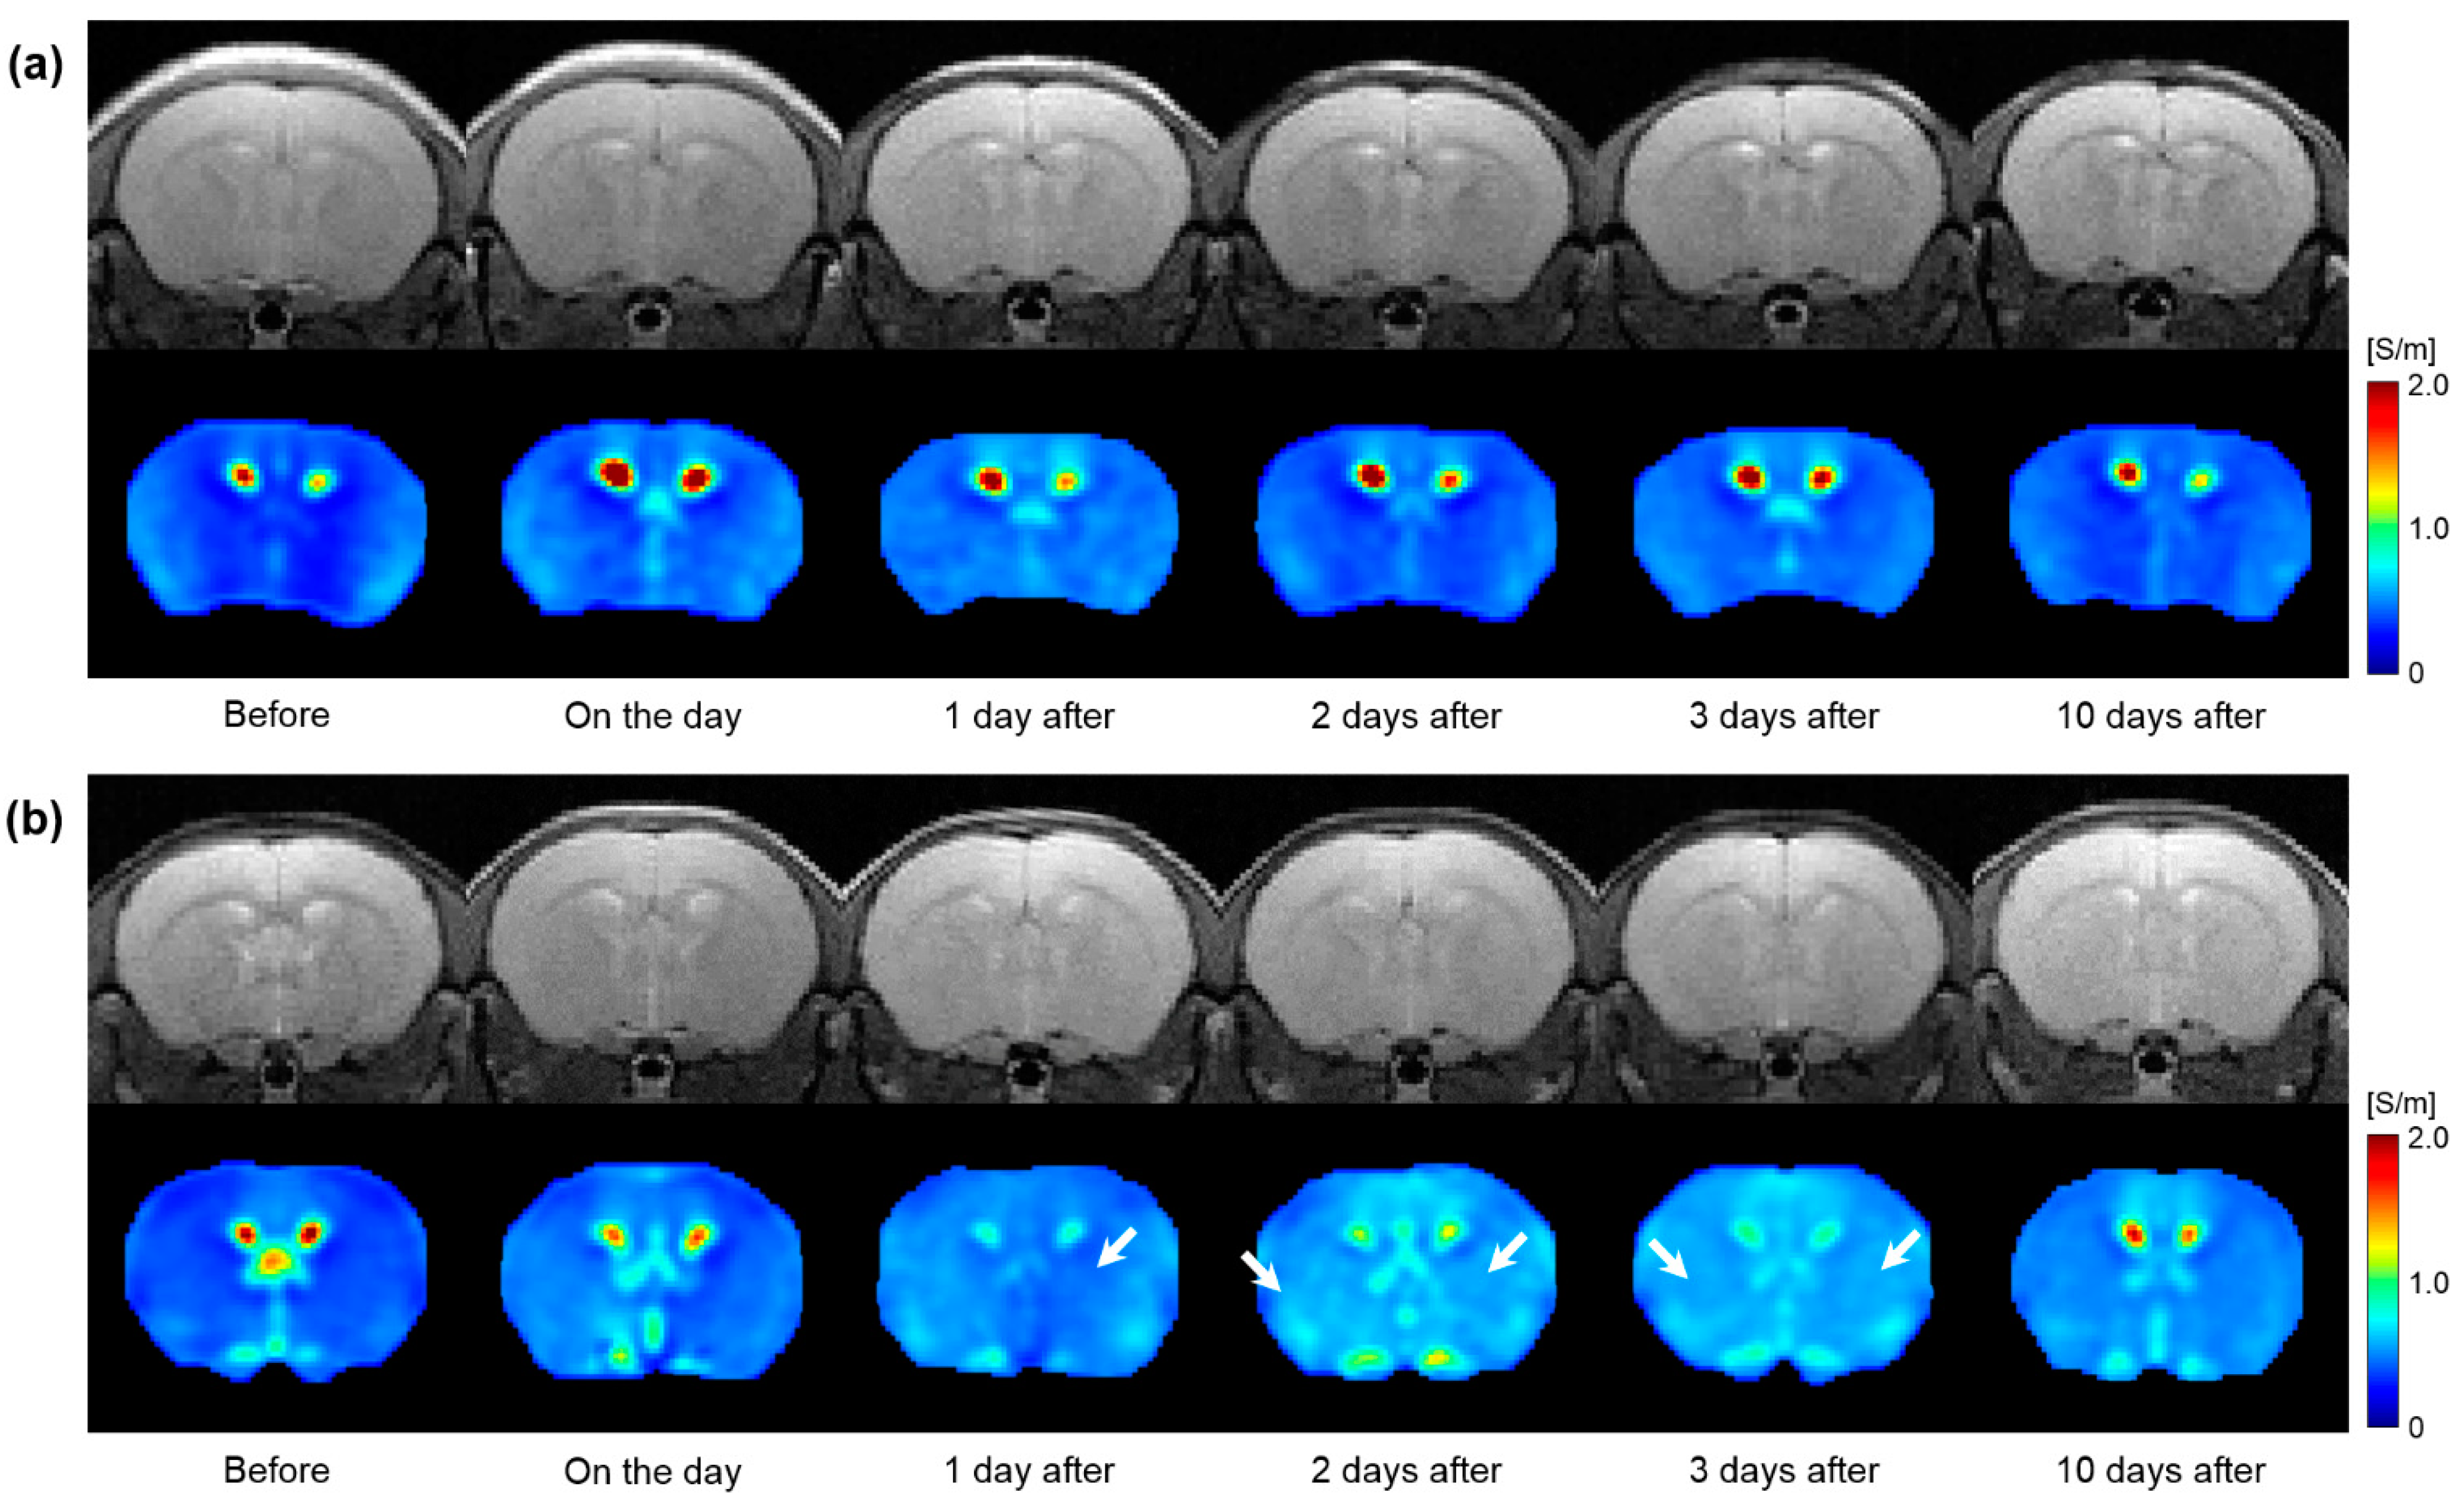

Figure 5 shows a full time-course image of T2WI and electrical conductivity of the in vivo mouse brains after irradiation. All images were obtained at 5 Gy and 10 Gy irradiation doses (Figure 5a,b). Compared to before irradiation, the morphological changes were not clearly observed in T2WI (first row) at both irradiation doses. However, the conductivity images showed different contrast variations depending on the irradiation doses (second row). Specifically, the conductivity of the 5 Gy dose showed a slight increase up to 1 day afterwards and a decrease to 10 days. On the contrary, the conductivity of the 10 Gy dose showed an increase in contrast up to 2 days after and gradually decreased to 10 days. When comparing the conductivity at 10 days post-irradiation, the 5 Gy dose showed a similar contrast to the pre-irradiation, but the 10 Gy dose still had a residual contrast.

Figure 5.

Time-course variations in T2-weighted and electrical conductivity images of in vivo mouse brains in response to 5 Gy (a) and 10 Gy (b) irradiation doses. White arrows indicate an increase in conductivity contrast.

From the in vivo mouse brain imaging results, the morphological differences were not clearly observed at different doses and elapsed times after irradiation. This can be inferred from the previous report that the changes in T2 relaxation time were within 10% despite the neutron-beam irradiation [18]. On the contrary, electrical conductivity clearly showed contrast changes with different doses and elapsed times after irradiation. In comparison, at a single time point after irradiation (Figure 4), the conductivity contrast was clearly distinguished at the 10 Gy dose from the other two lower doses. This indicates the reliability of electrical conductivity in that 10 Gy is an appropriate dose calculated considering the weight of the mouse [6]. In addition, the conductivity contrast of 10 Gy showed a different pattern with the elapsed time (Figure 5). Unlike the other two doses, the conductivity of 10 Gy showed a more sustained tissue response and residual conductivity even 10 days after irradiation.